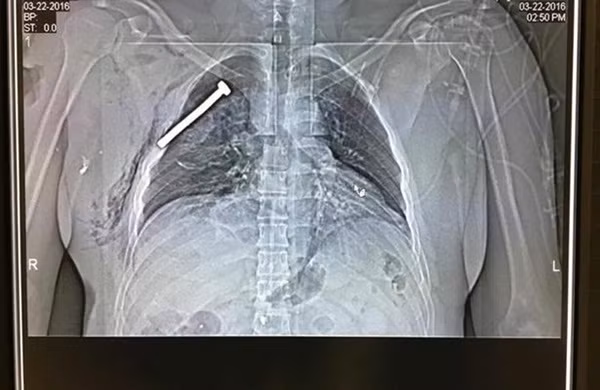

Những mảnh kim loại xoắn được găm chặt trong cơ thể của nhiều nạn nhân may mắn sống sót sau vụ đánh bom khủng bố ở Bỉ hôm 22-3

Hình ảnh về những mảnh kim loại xoắn dính máu sau các cuộc phẫu thuật, ảnh chụp X-quang thấy đinh ghim sâu trong ngực con người, ốc vít han gỉ nằm sâu trong bắp đùi khiến người ta rùng mình về độ tàn nhẫn, dã man của phiến quân khủng bố.

Ảnh chụp X-quang cho thấy một chiếc đinh nhọn găm chặt vào trong lồng ngực của nạn nhân

Những kẻ đánh bom tự sát đã nhồi đinh vào trong bom để làm tăng tính sát thương khi kích nổ chúng